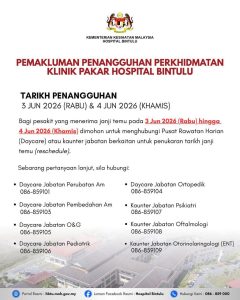

BINTULU: Perkhidmatan klinik pakar di Hospital Bintulu akan ditangguhkan sempena Hari Kelepasan Am Hari Gawai dan Hari...